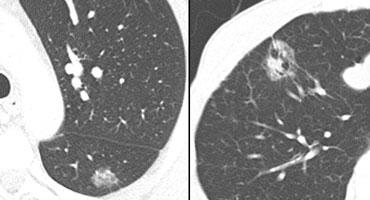

Bờ tổn thương

- Dấu hiệu corona radiata – liên quan chặt chẽ với ác tính (hình minh họa)

- Bờ múi hoặc bờ lượn sóng – khả năng trung gian

- Bờ nhẵn – nhiều khả năng lành tính trừ khi có nguồn gốc di căn